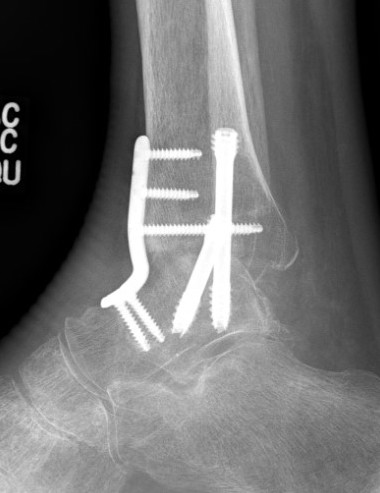

Anterior approach

Technique

Anterior midline approach

- between tibialis anterior and EHL

- tibia and talar pins and ankle distractor

- debride joint surfaces

- fix with anatomically contoured anterior plate + screws